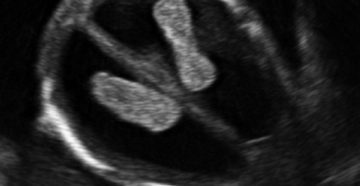

Узи на 6-й неделе беременности: показания и порядок выполнения Большинство женщин узнает о своем интересном…